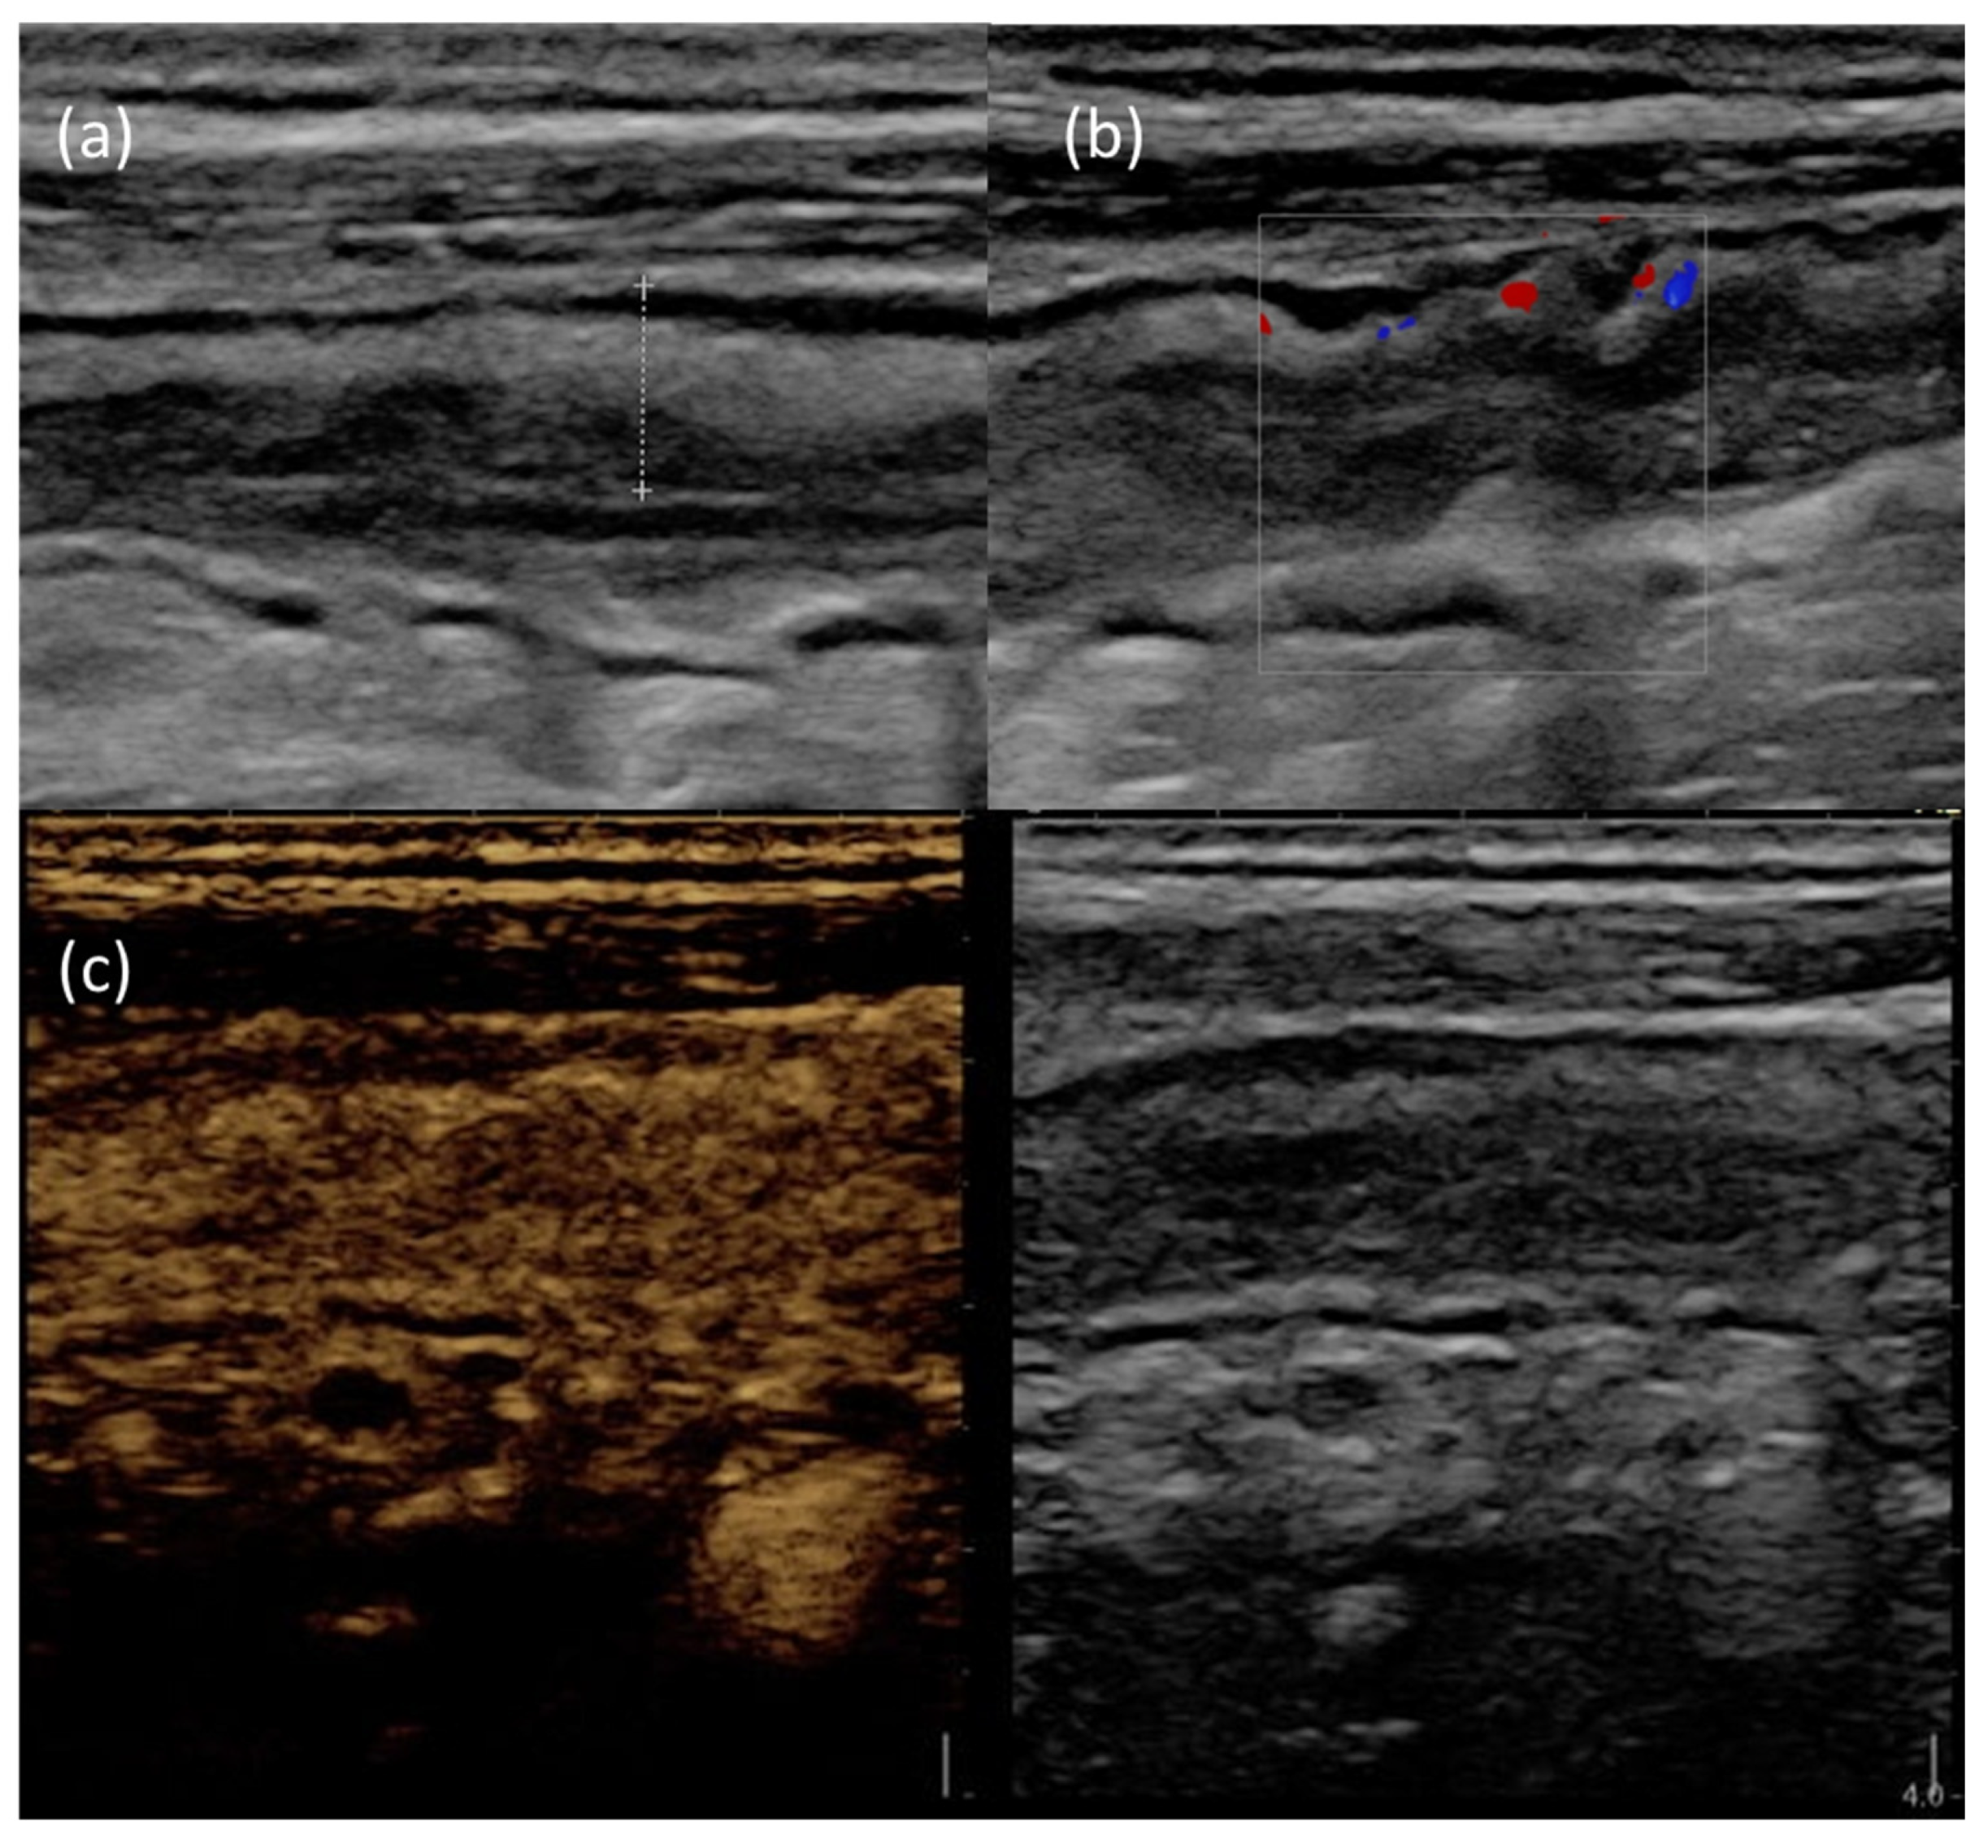

- Greis, C. Technology overview: SonoVue (Bracco, Milan). Eur. Radiol. 2004, 14 (Suppl. S8), P11–P15. [Google Scholar] [PubMed]

- Mocci, G.; Migaleddu, V.; Cabras, F.; Sirigu, D.; Scanu, D.; Virgilio, G.; Marzo, M. SICUS and CEUS imaging in Crohn’s disease: An update. J. Ultrasound 2017, 20, 1–9. [Google Scholar] [CrossRef] [PubMed]

- Saevik, F.; Nylund, K.; Hausken, T.; Ødegaard, S.; Gilja, O.H. Bowel perfusion measured with dynamic contrast-enhanced ultrasound predicts treatment outcome in patients with Crohn’s disease. Inflamm. Bowel Dis. 2014, 20, 2029–2037. [Google Scholar] [CrossRef] [PubMed]

- Quaia, E.; Gennari, A.G.; Cova, M.A. Early Predictors of the Long-term Response to Therapy in Patients With Crohn Disease Derived From a Time-Intensity Curve Analysis After Microbubble Contrast Agent Injection. J. Ultrasound Med. Off. J. Am. Inst. Ultrasound Med. 2019, 38, 947–958. [Google Scholar] [CrossRef]

- Laterza, L.; Ainora, M.E.; Garcovich, M.; Galasso, L.; Poscia, A.; Di Stasio, E.; Lupascu, A.; Riccardi, L.; Scaldaferri, F.; Armuzzi, A.; et al. Bowel contrast-enhanced ultrasound perfusion imaging in the evaluation of Crohn’s disease patients undergoing anti-TNFα therapy. Dig. Liver Dis. 2021, 53, 729–737. [Google Scholar] [CrossRef]

- Zorzi, F.; Ghosh, S.; Chiaramonte, C.; Lolli, E.; Ventura, M.; Onali, S.; De Cristofaro, E.; Fantini, M.C.; Biancone, L.; Monteleone, G.; et al. Response Assessed by Ultrasonography as Target of Biological Treatment for Crohn’s Disease. Clin. Gastroenterol. Hepatol. 2020, 18, 2030–2037. [Google Scholar] [CrossRef]